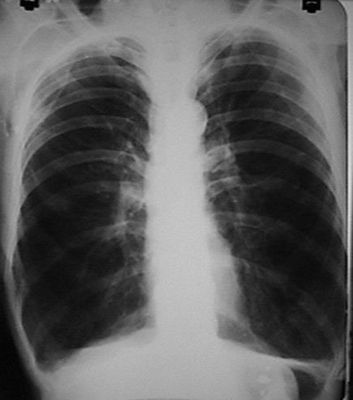

Question 19

Question

patología que se observa en la radiografía.

Answer

• sx condensacion

• neumonia

• enfisema pulmonar

• derrame pleural